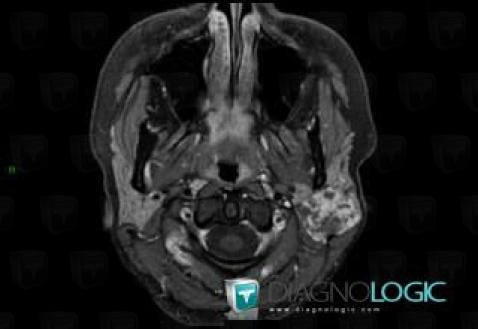

Pleomorphic adenoma, Parotid and other salivary glands, MRI

Here is the specific information in the key image above:

- Diagnosis Pleomorphic adenoma, Location(s) Parotid and other salivary glands, with gamuts Parotid gland lesion / enlargement, Neoplasic parotid gland lesion